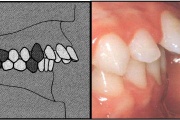

Ravijärgne seis. Jäävhammas on täielikult lõikunud.

Esimese jäävmolaari ektoopiline lõikumine